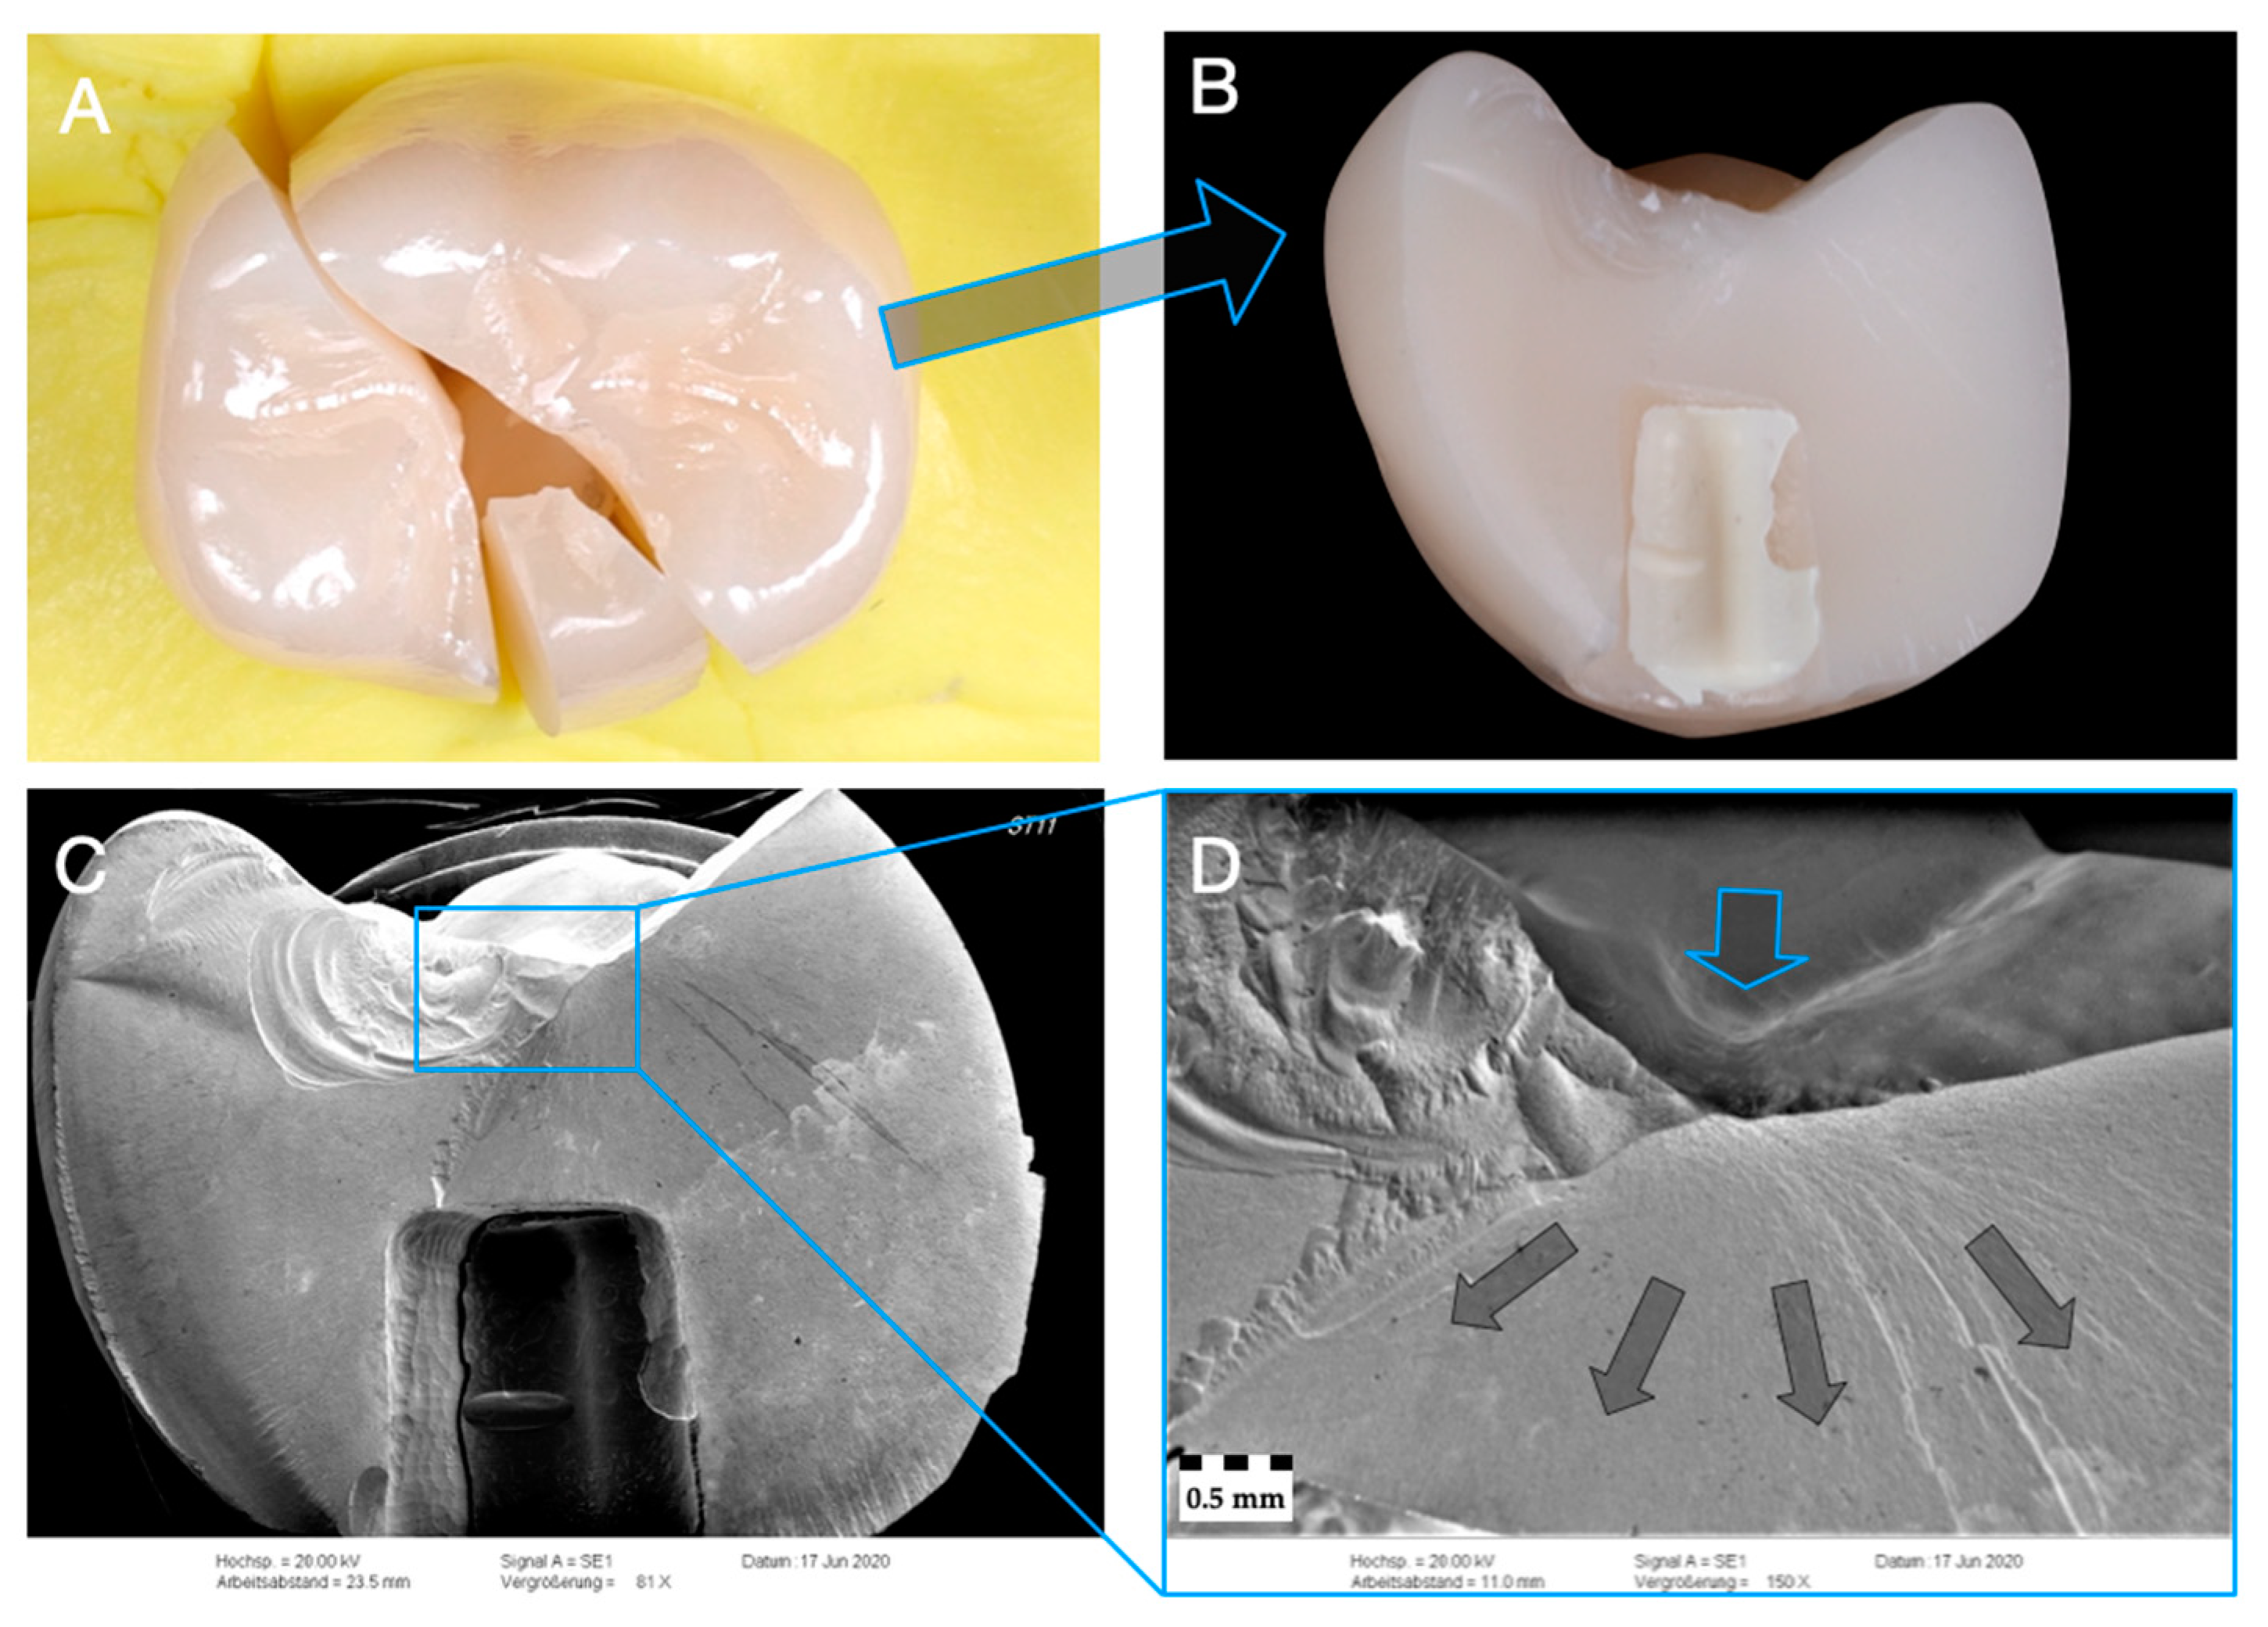

3.3. Failure and Fractographic Analysis after Single-Load-To-Failure Testing

- Irrespective of the material used in monolithic application, zirconia (Z-HT, Z-ST, Z-XT) and PICN restorations failed mostly from bulk fractures. When PICN was used as a table top, fracture was limited to PICN, whereas the 3Y-TZP framework remained intact.